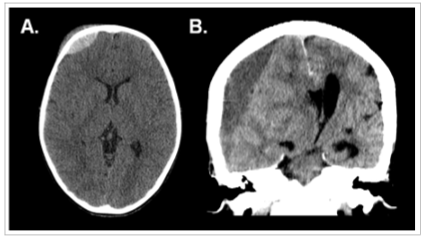

As imagens a seguir referem-se a dois pacientes diferentes, previamente hígidos, com traumatismo cranioencefálico.

Em relação às características das lesões intracranianas evidenciadas tem-se que: